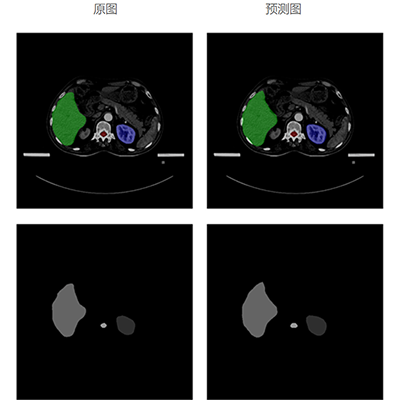

模型经过对海量勾画结构数据的学习,以及改进优化,再进过大量样本数据训练及验证,自动勾画结果的平均准确度已达92%以上。

自动勾画效果